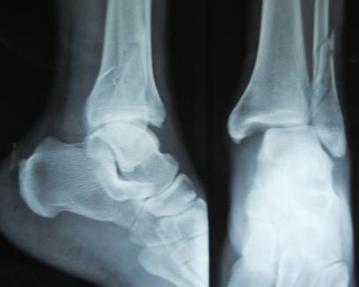

♥踝关节脱位

因距骨体处于踝穴中,周围有坚强的韧带包绕,牢固稳定,故单纯踝关节脱位极为罕见,多合并有骨折。本节讨论的是以脱位为主,合并有较轻微骨折的踝部损伤,简称为踝关节脱位[1](dislocation of ankle joint),此种损伤以后脱位最多见,前脱位次之,向上脱位最为少见。

受伤后踝部即出现疼痛、肿胀、畸形和触痛。